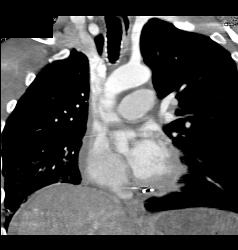

GSW With Bullets Near Heart